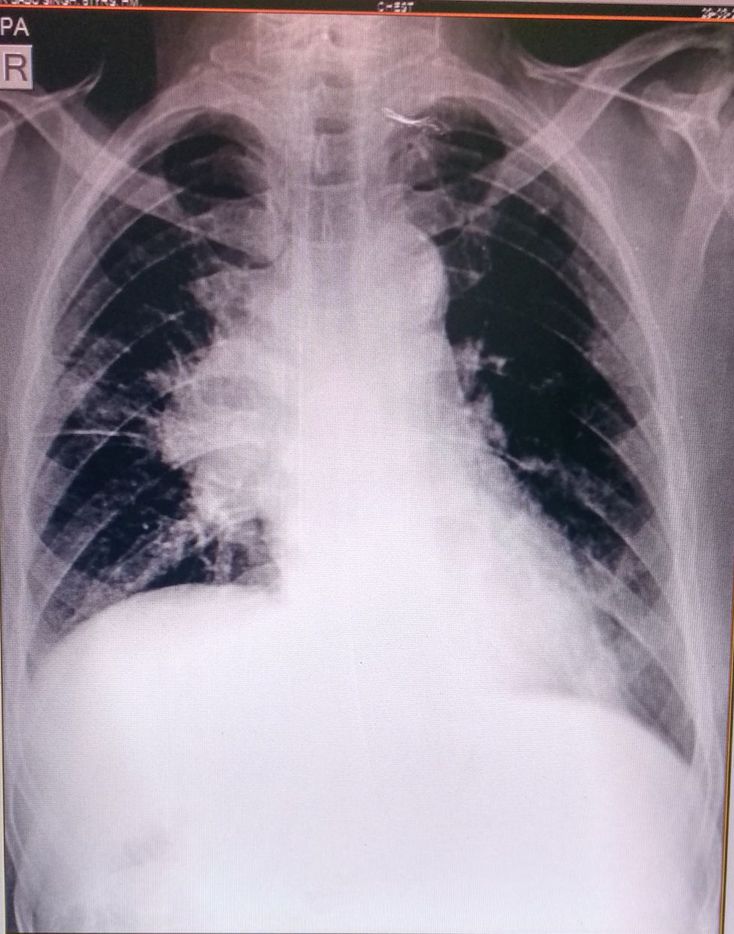

Superior vena cava syndrome (SVCS), is a group of symptoms caused by obstruction of the superior vena cava (a short, wide vessel carrying circulating blood into the heart). More than 80% of cases of SVCS are caused by compression of the vessel wall by malignant tumors in the mediastinum, the vast majority of which are either lung canceror non-Hodgkin's lymphoma. Non-malignant causes include benign mediastinal tumors, aortic aneurysm, infections, thrombosis due to central venous catheter placement, and fibrosing mediastinitis. 🎯Signs and symptoms Shortness of breath is the most common symptom, followed by face or arm swelling. Following are frequent symptoms: ➡️Difficulty breathing ➡️Headache ➡️Facial swelling ➡️Venous distention in the neck and distended veins in the upper chest and arms ➡️Upper limb edema ➡️Lightheadedness ➡️Cough ➡️Edema (swelling) of the neck, called the collar of Stokes ➡️Pemberton's sign